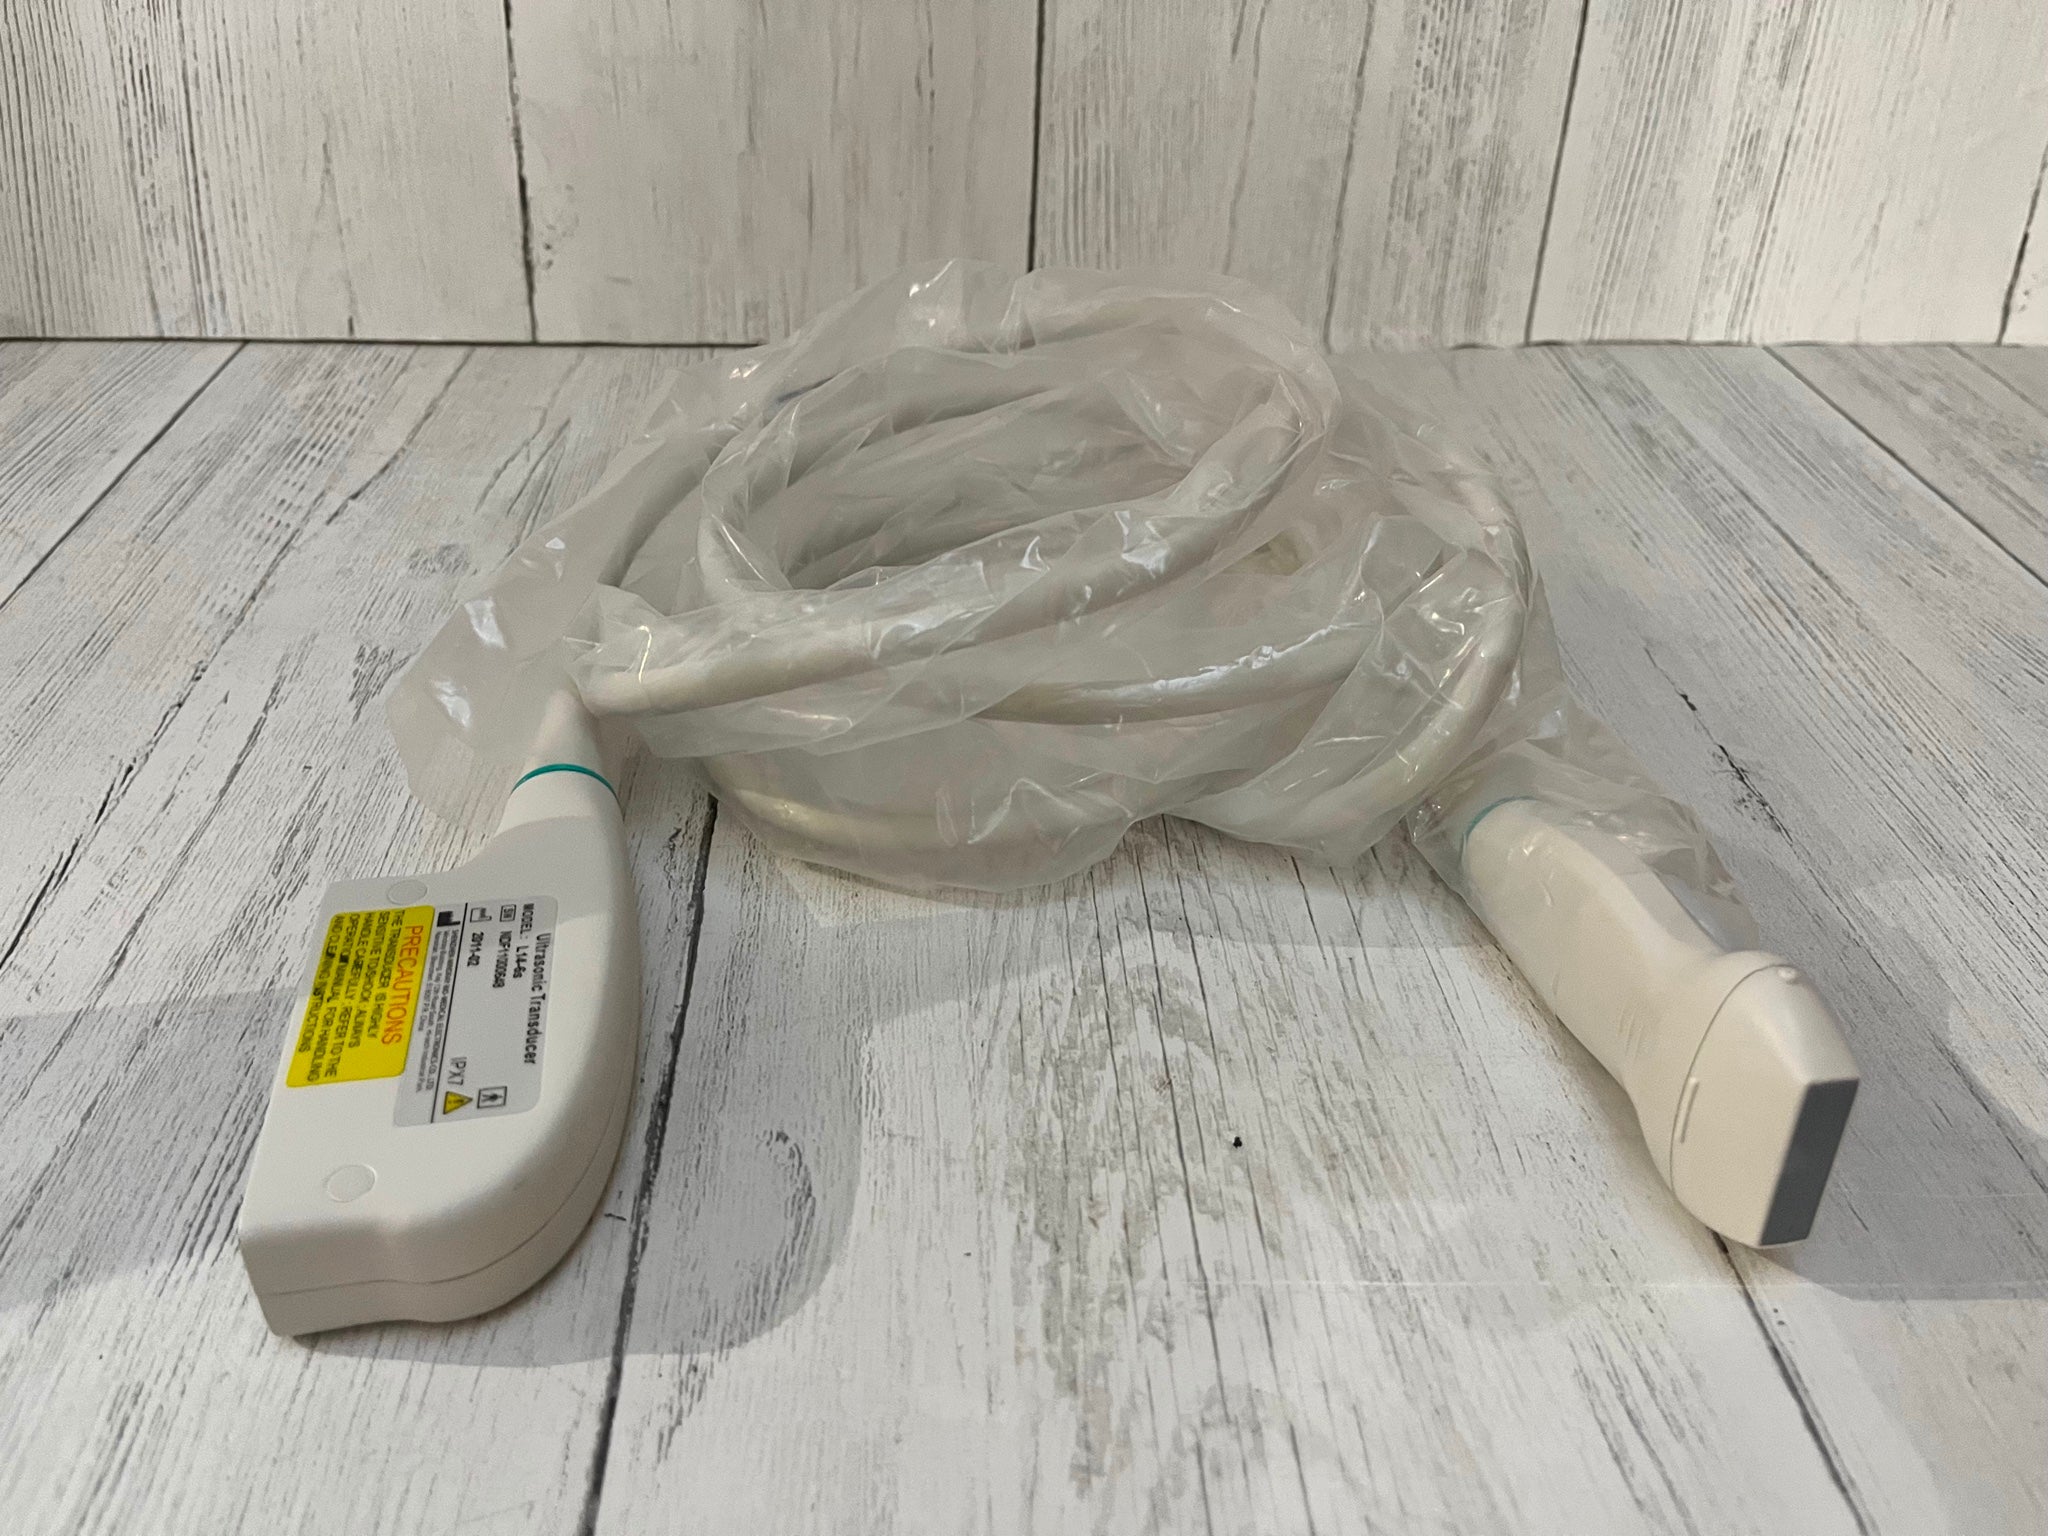

Veterinary Ultrasound Machine,VET Laptop Ultrasound scanner,7.5Mhz Rectal Probe

Veterinary Ultrasound Machine,VET Laptop Ultrasound scanner,7.5Mhz Rectal Probe 670924011996